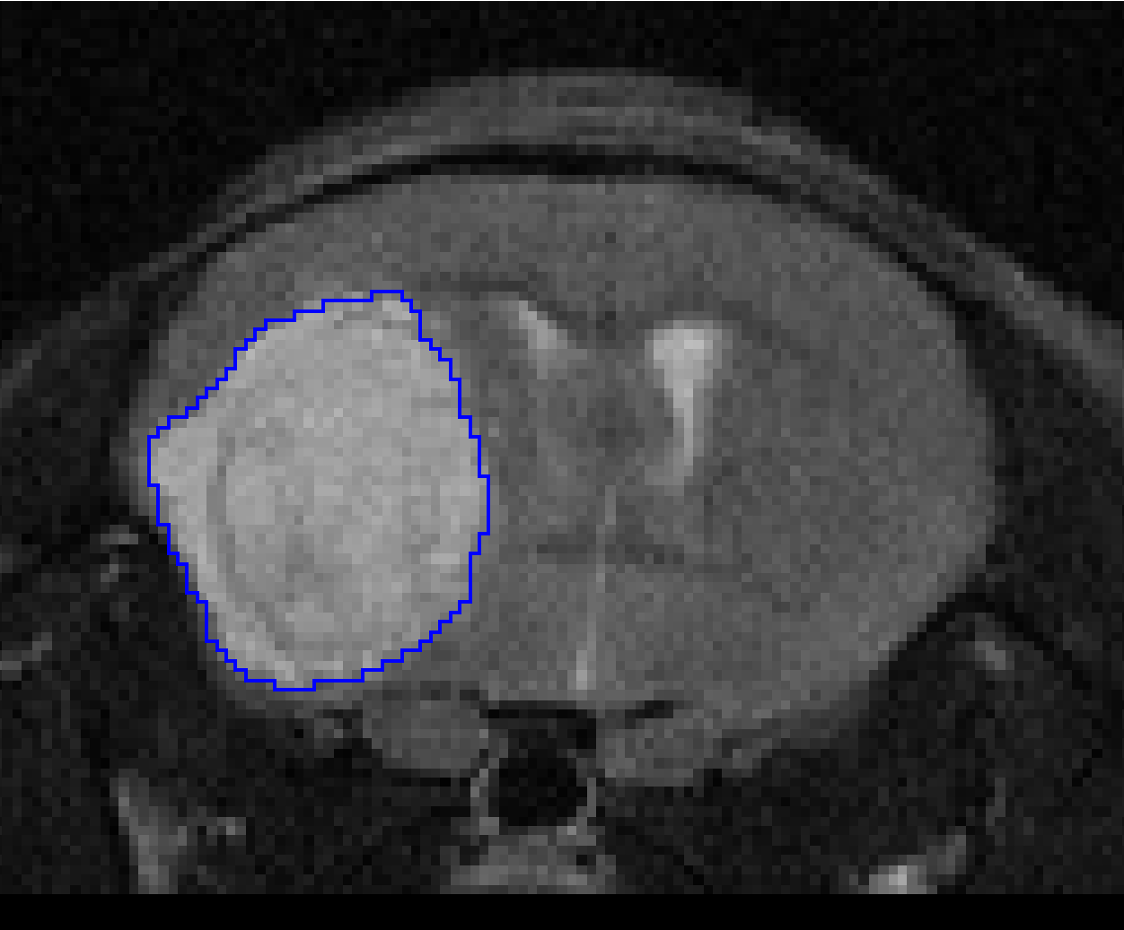

pmod’s tools provide comprehensive workflows for post-processing and quantification of imaging data for fundamental oncology research, development of radiotracers and theranostics, and in clinical research studies. Imaging scientists can trust pmod to reproducibly read their data, interpret the meta-data/units and help users calculate statistics such as SUV for their studies and publications.

• Multimodality segmentation tools – comprehensive semi-automated and manual tools for precision and reproducibility

• Full access to metadata – ensure accurate calculation of Standard Uptake Value and other key statistics